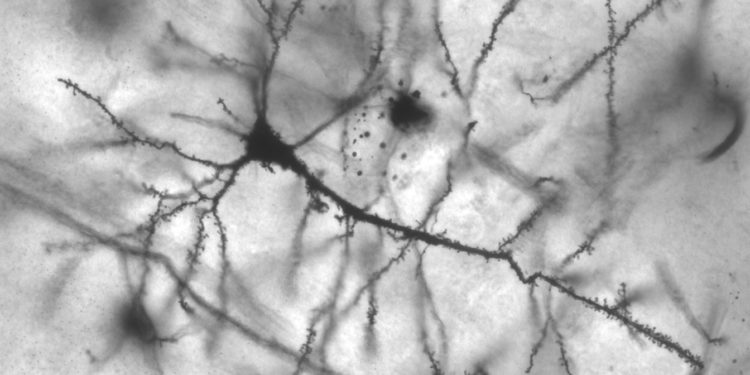

Oggetti di studio sono stati dei topi in cui sia l’università americana che quella giapponese hanno tenuto sotto controllo circa 3000 geni, stimolati uno per uno in modo da evidenziarne le funzioni. E qui sono comparsi i comportamenti dei geni CD22 e COL17A1. Il primo gestisce infatti l’attività delle cellule spazzino del cervello, quelle della microglia, a difesa del sistema nervoso centrale, e la seconda, che controlla lo sviluppo delle cellule staminali della pelle. Nel caso del CD22 in effetti, lo studio della Stanford University ha evidenziato una forte iperattività del gene che, aumentando la produzione della proteina, impedisce un corretto svolgimento delle attività di pulizia del sistema nervoso ed in particolare del cervello.

Ed è qui che arriva l’azione degli scienziati, che tramite un anticorpo specifico hanno bloccato l’attività del gene, riscontrando una sorprendente ripresa delle attività cerebrali nei topi più anziani. Merito delle cellule spazzino che, riuscendo a lavorare in maniera più ottimale, hanno aumentato la loro efficienza esattamente come quelle dei topi più giovani. È facile quindi immaginare le possibili ripercussioni nel mondo scientifico se si pensa che tale situazione potrebbe replicarsi anche nell’uomo e magari trovare delle risposte all’Alzehimer e al Parkinson.